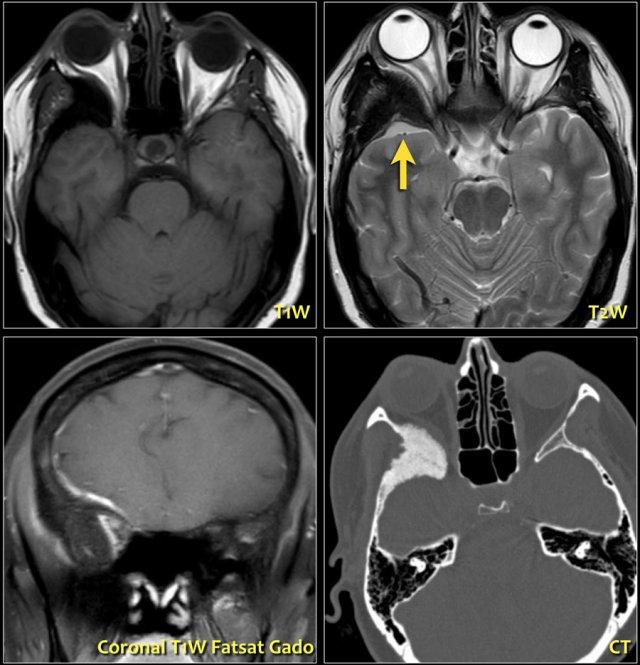

Hãy quan sát hình ảnh trước, sau đó chúng ta sẽ thảo luận chi tiết hơn.

Trên hình bên trái, thần kinh thị giác bên phải có hình ảnh bình thường.

Lưu ý rằng thần kinh thị giác là một bó chất trắng.

Nó có cùng cường độ tín hiệu với chất trắng trong não.

Ở phía đối bên, thần kinh thị giác có tín hiệu tăng cao.

Đây là tổn thương ngoài nhãn cầu trong nón cơ, và chúng ta cần nghĩ đến các bệnh lý tân sinh so với bệnh lý mất myelin.

Tiếp tục xem hình ảnh tiếp theo.Bên trái là hình ảnh chuỗi xung FLAIR kết hợp kỹ thuật ức chế mỡ (fat-sat).

Lưu ý tín hiệu bất thường và thực tế là thần kinh thị giác không bị phì đại, điều này giúp loại trừ khả năng u.Hình ảnh tủy sống cổ cho thấy một đoạn dài tổn thương không chiếm chỗ.

Dựa trên các hình ảnh này, chẩn đoán phân biệt bao gồm xơ cứng rải rác (MS) và hội chứng Devic (còn gọi là viêm tủy thị thần kinh).

Do MS phổ biến hơn nhiều, đây sẽ là chẩn đoán có khả năng nhất, nhưng trường hợp này thực tế là hội chứng Devic.Một số tác giả coi hội chứng Devic là một thể của MS, tuy nhiên hội chứng Devic khác với MS ở các điểm sau:

- Bệnh nhân có tình trạng rất nặng, do hội chứng Devic có diễn tiến cấp tính và ác tính hơn.

- Thường có sự kết hợp giữa mù một mắt và liệt hai chi dưới do tổn thương viêm tủy cắt ngang đoạn dài (trong MS thường chỉ một hoặc hai đoạn).

- Hội chứng Devic thường có diễn tiến đơn pha.

- Thường không có mảng xơ cứng ở não.

Bên trái là hình ảnh của một bệnh nhân khác, cũng có viêm thần kinh thị giác.

Có tín hiệu tăng trong thần kinh thị giác và trong não có nhiều tổn thương là hậu quả của MS.

Các tổn thương này không xuất hiện cùng một thời điểm, do đó có sự phân tán theo thời gian và không gian, đây là đặc điểm đặc trưng của MS.-

50% bệnh nhân viêm thần kinh thị giác cuối cùng sẽ tiến triển thành MS.

50% còn lại có viêm thần kinh thị giác đơn độc (xem chẩn đoán phân biệt ở trên). - 80% bệnh nhân MS sẽ có biểu hiện viêm thần kinh thị giác tại một thời điểm nào đó trong quá trình bệnh.